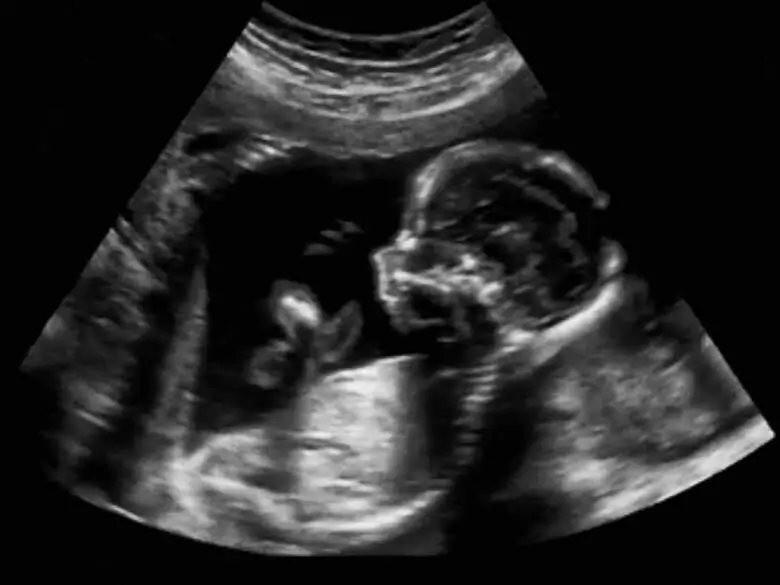

Trastornos del crecimiento fetal

Feto

El retraso del crecimiento intrauterino (RCIU) se introdujo en 1961 y se refiere a un feto que no ha alcanzado su potencial durante su vida fetal.